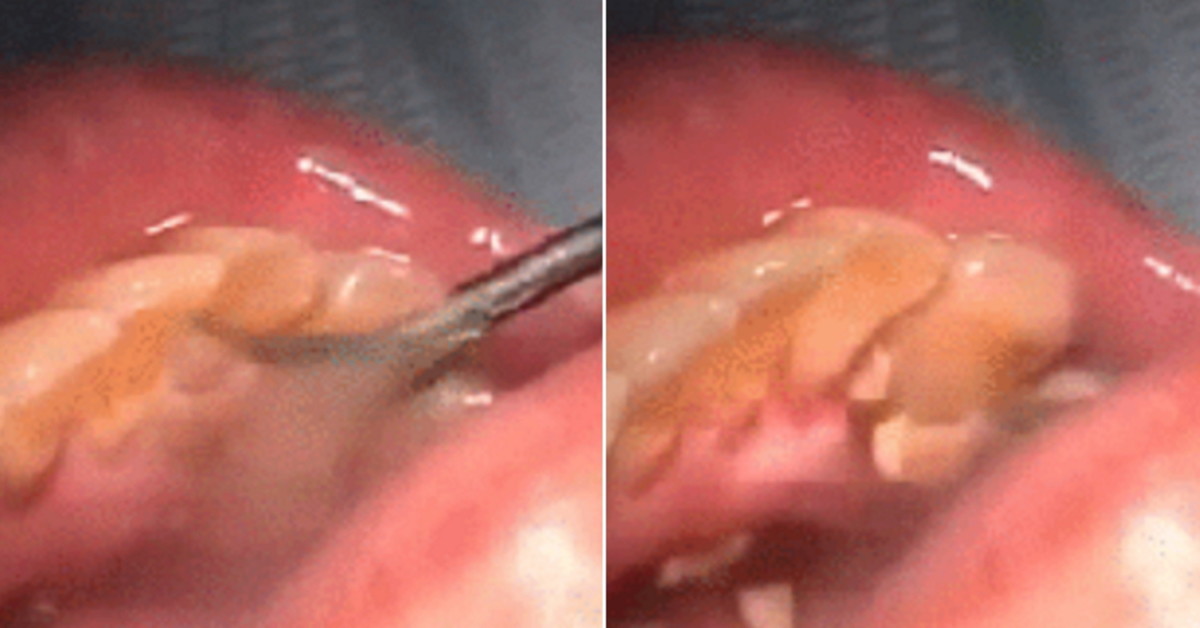

최근 이미지 공유 사이트 이머저에는 치석을 말끔하게 제거하는 스케일링 시술 과정이 공개됐다.

공개된 영상 속에는 의사가 뾰족한 날이 달린 도구로 환자의 치아에 달라붙은 치석을 제거하고 있다.

의사의 손길이 닿을 때마다 환자의 잇몸 구석구석을 촘촘하게 채우고 있었던 치석은 시원하게 떨어져 내린다.

착색 때문에 '누렁니'로 보이게 만들었던 지긋지긋한 치석이 사라지자 치아는 말끔한 모습을 되찾았다.